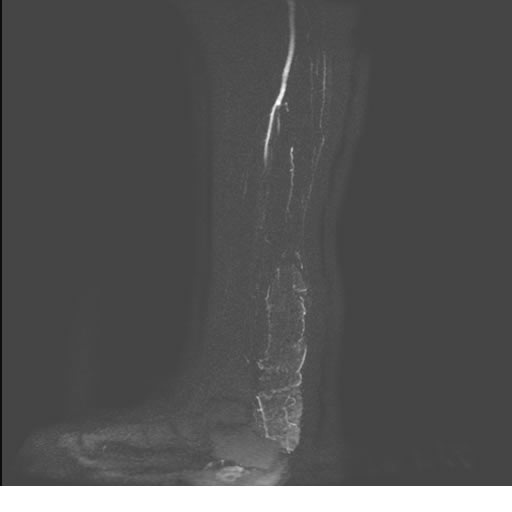

Se realiza estudio de MRI de pierna izquierda, utilizando secuencias Spin Echo y GRE en diferentes planos, se realiza angio MRI en fase arterial y venosa de pierna izquierda

El estudio demuestra masa a nivel de los músculos gemelos, más evidente en secuencia con pulso de saturación de grasa, en el estudio de angio resonancia de pierna la fase arterial no muestra ninguna anormalidad, en la fase venosa se observa acumulo del medio de contraste a este nivel.

Se concluye que se observa una masa de tejido muscular sumamente vascularizada compatible con un hemangioarcoma.